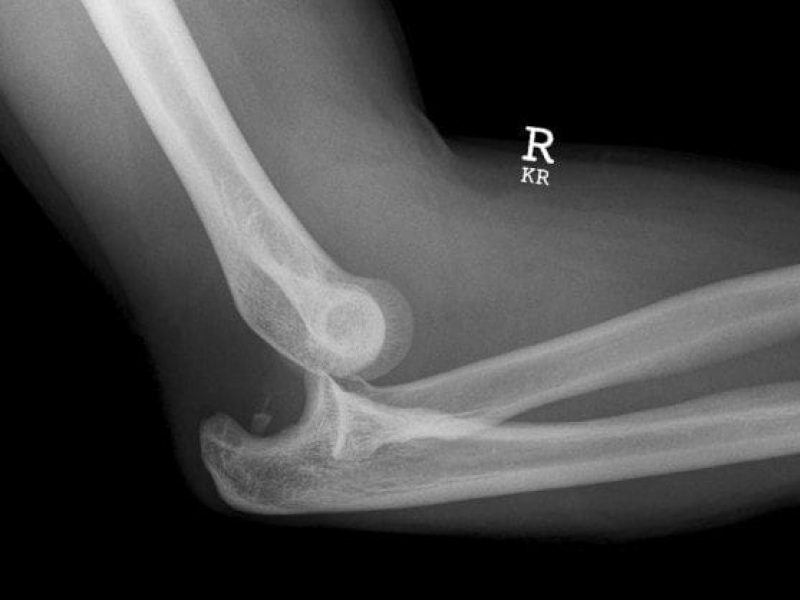

63 year old male with PMHx of HTN, DM, COPD p/w right elbow